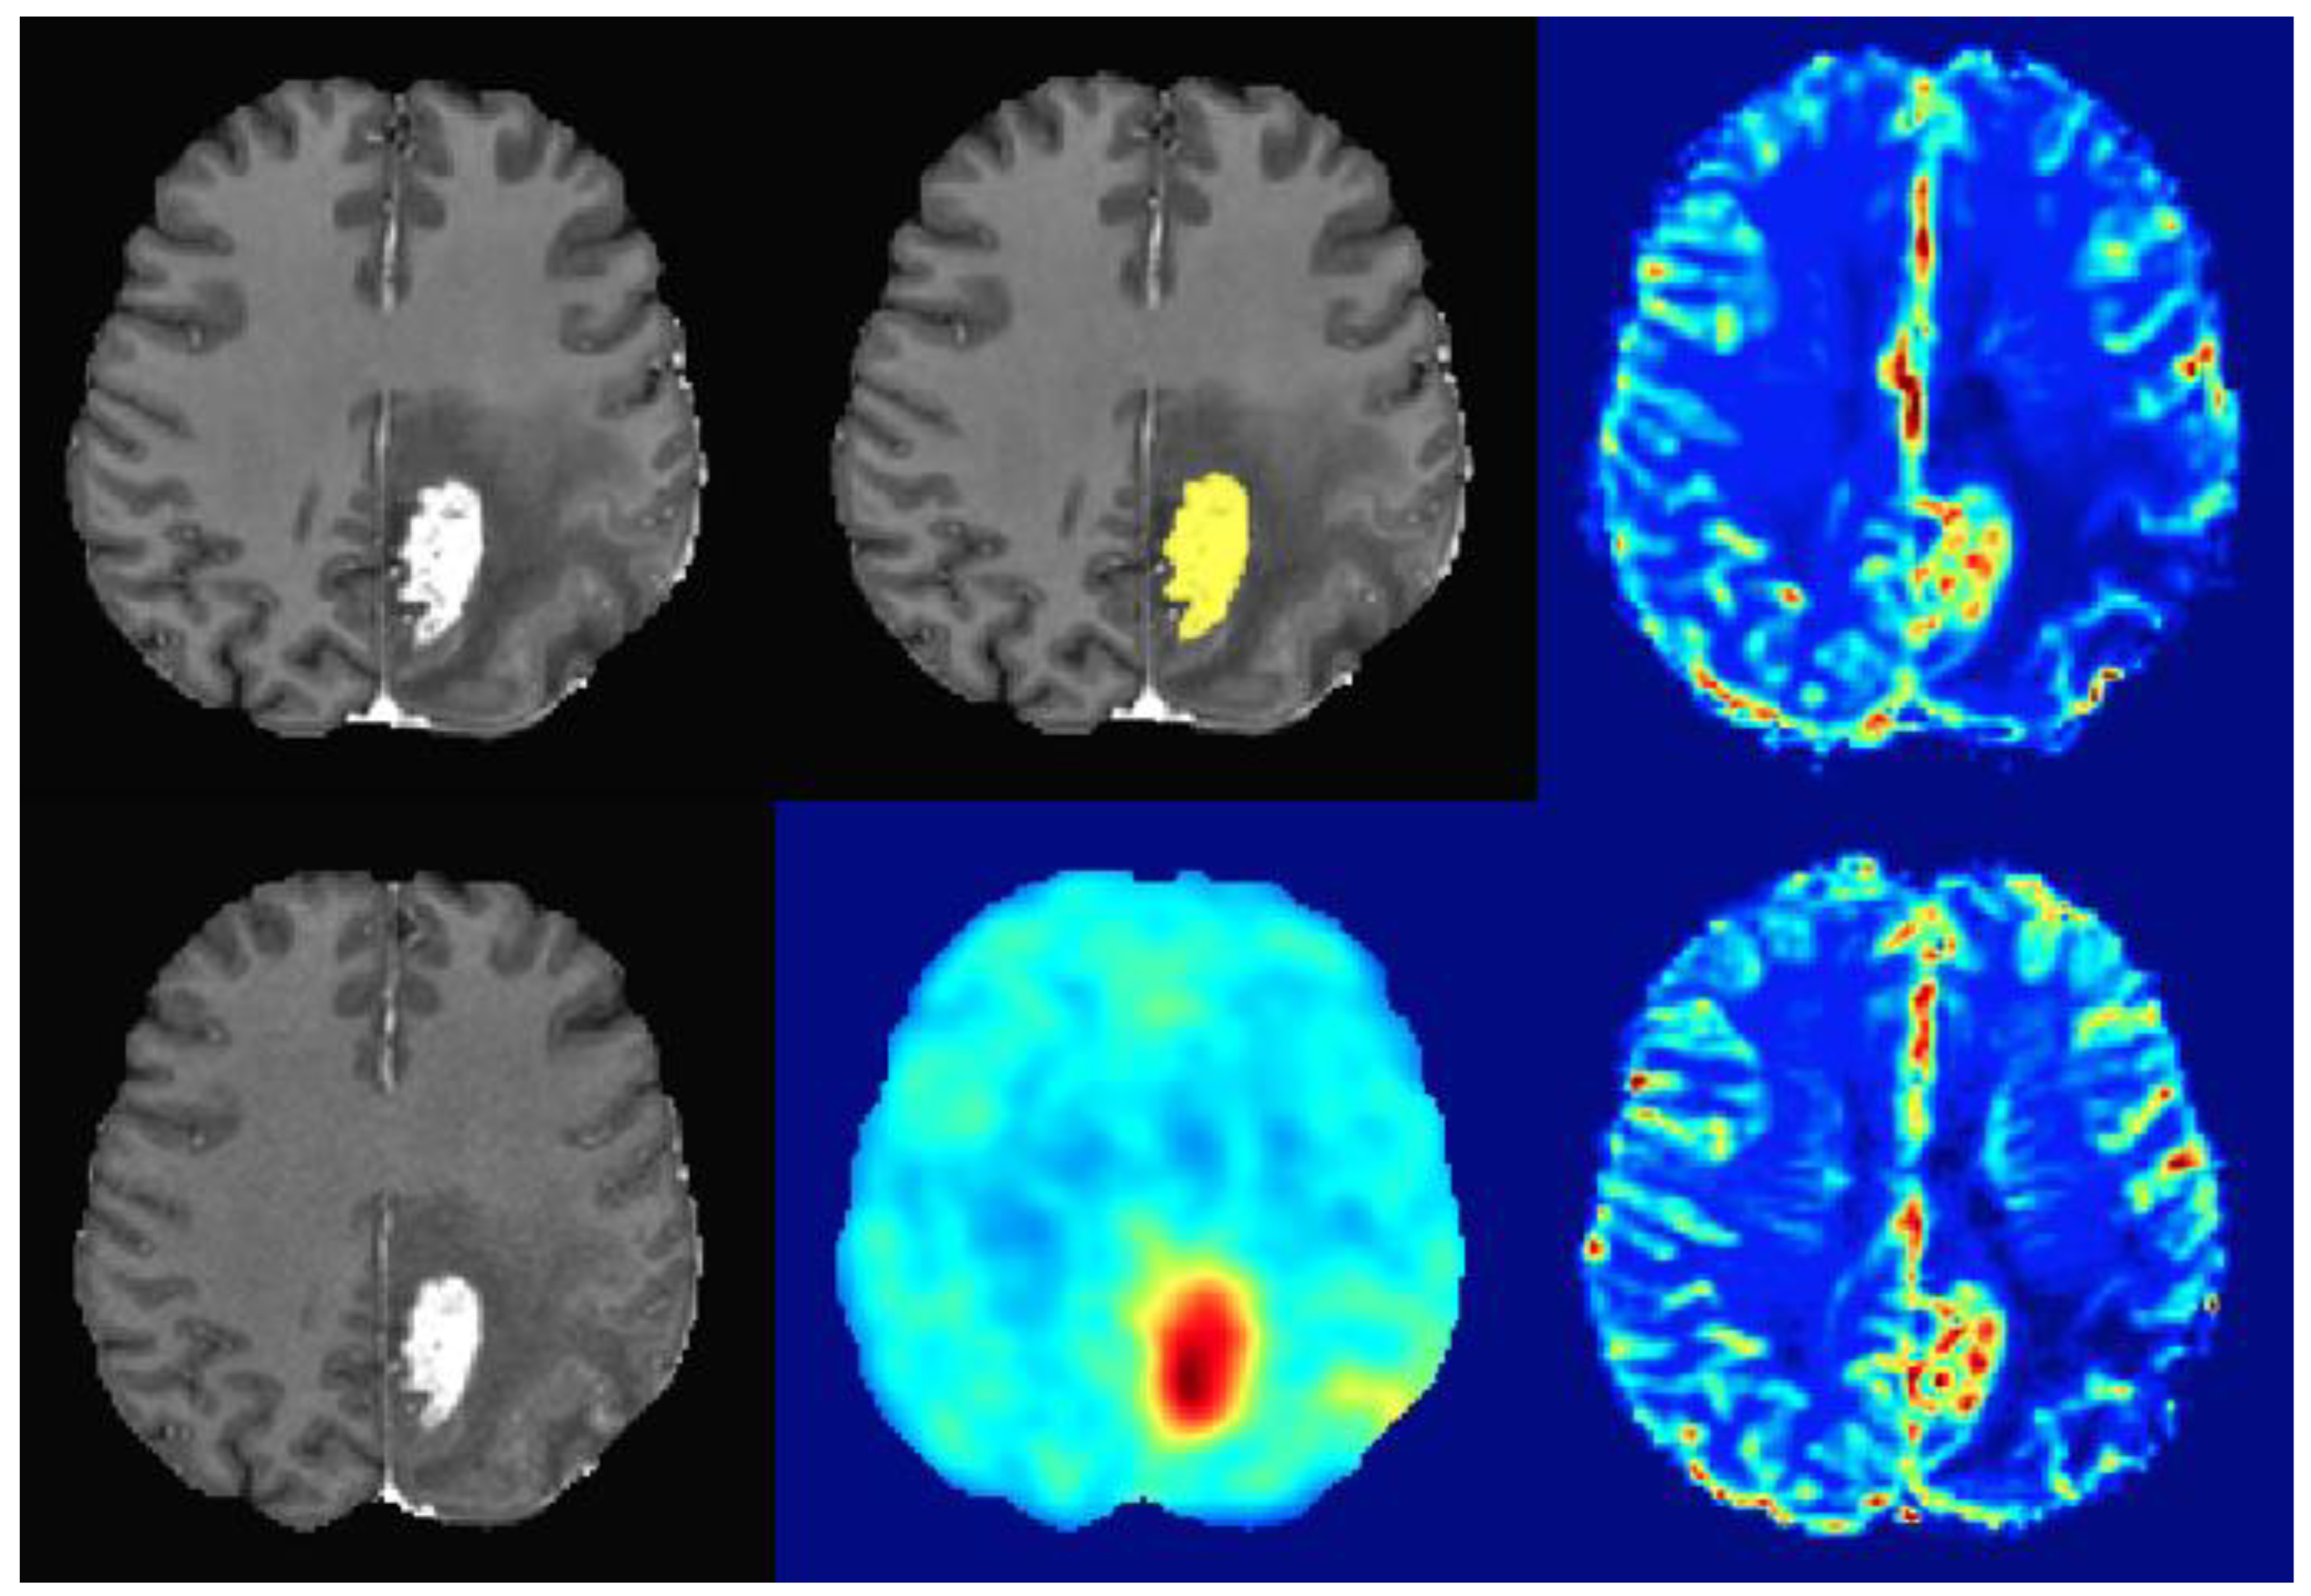

2.3. Image Analysis

3.2. Spatial Overlap, Mutual Information, and Spearman Correlation of Imaging Hotspots

- Schön, S.; Cabello, J.; Liesche-Starnecker, F.; Molina-Romero, M.; Eichinger, P.; Metz, M.; Karimov, I.; Preibisch, C.; Keupp, J.; Hock, A.; et al. Imaging Glioma Biology: Spatial Comparison of Amino Acid PET, Amide Proton Transfer, and Perfusion-Weighted MRI in Newly Diagnosed Gliomas. Eur. J. Nucl. Med. Mol. Imaging 2020, 47, 1468–1475. [Google Scholar] [CrossRef]